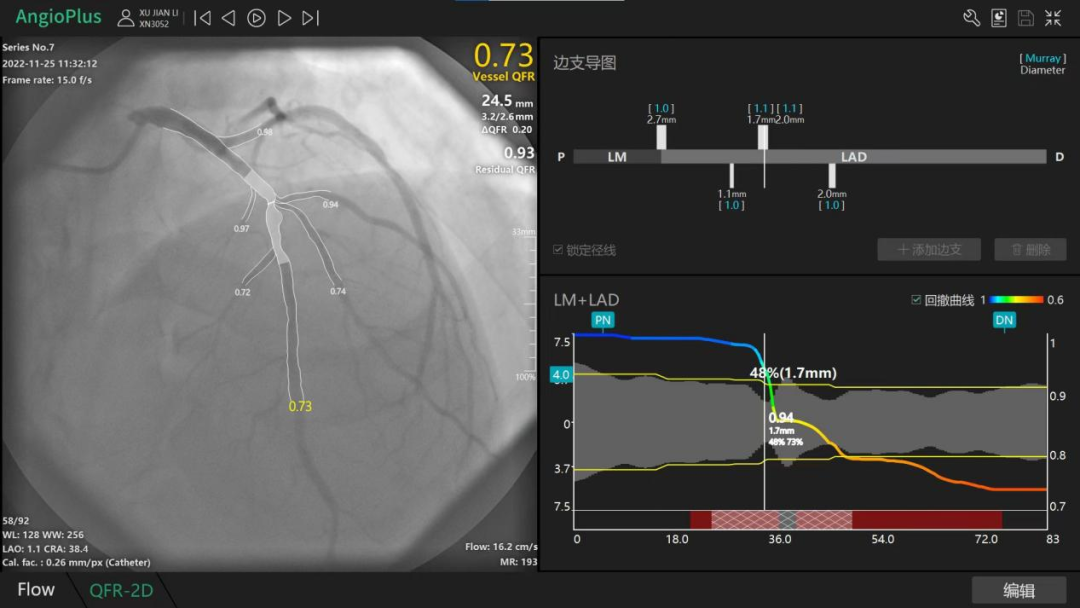

为进一步明确患者该处狭窄病变是否引起心肌缺血,心病科介入团队决定对患者予以QRF测定,结果显示前降支测值为0.73,对角支测值0.74,表明患者胸痛与心肌缺血有关,冠脉血流储备不足,具有介入治疗指征。

随后,在QRF新技术的指导下,精确预设支架位置、尺寸,心病科介入团队为患者在前降支植入支架1枚,对角支植入药物球囊1枚,术后复查QRF值均提升为0.91。目前患者恢复良好,已无明显的胸闷胸痛症状。